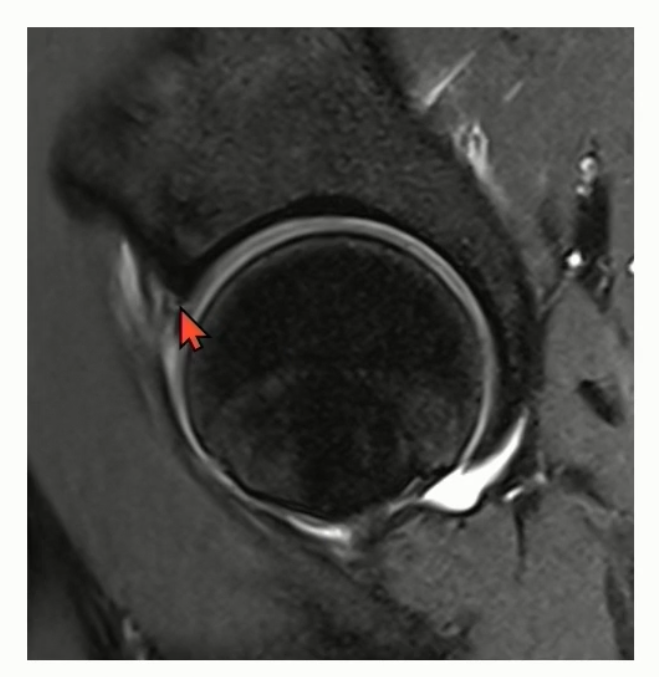

Case 1)

antero-superior labrum에 발생한 detachment 소견